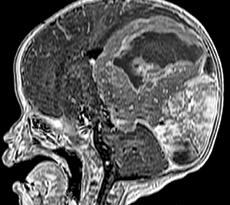

El Departamento de Neurocirugía Pediátrica de dicha institución ha brindado sus servicios desde hace más de 40 años, inicialmente por neurocirujanos generales y en la actualidad se encuentra liderada por neurocirujanos pediatras. Actualmente ofrece tratamiento a diversos padecimientos como lo son la hidrocefalia congénita, craneosinostosis, disrafismos, traumatismos craneoencefálicos, tumores cerebrales, entre otros, además de contar con la tecnología de última generación para este fin, como lo es la Neuronavegación, Neuroendoscopia, entre otros. También se encuentra trabajando arduamente para obtener el aval universitario y de esa manera lograr la creación de la residencia médica en un futuro muy próximo y así poder ser una sede hospitalaria más para la formación de médicos especialistas en esta disciplina. Asimismo, está trabajando para crear la Clínica de Cirugía Craneofacial pediátrica, entre otros proyectos.